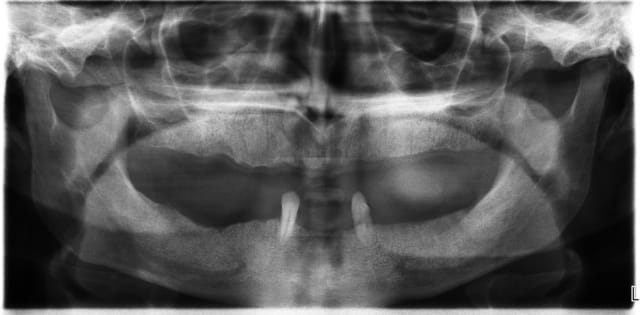

3ème photo: radio d´un patient âgé de 73 ans qui souhaitait avoir des dents fixées.Comme on l´observe il n a plus de place après les foramines mentales.Nous avons donc utilisé juste l´os interforaminal. Nous avons suivi le concept du prof. Nentwig qui consiste à pouvoir ajouter 2 dents dans chaque quadrant dans la mandibule.

Je sais bien que 8 implants auraient suffit cependant 10 ont été posés.Nous voulions remplacer chaque racine avec un implant.

Le patient n a jamais eu de problèmes ( juste avec une hygiène buccale normale, brosse à dents).

Les deux dernières photos montrent le même cas deux ans plus tard.